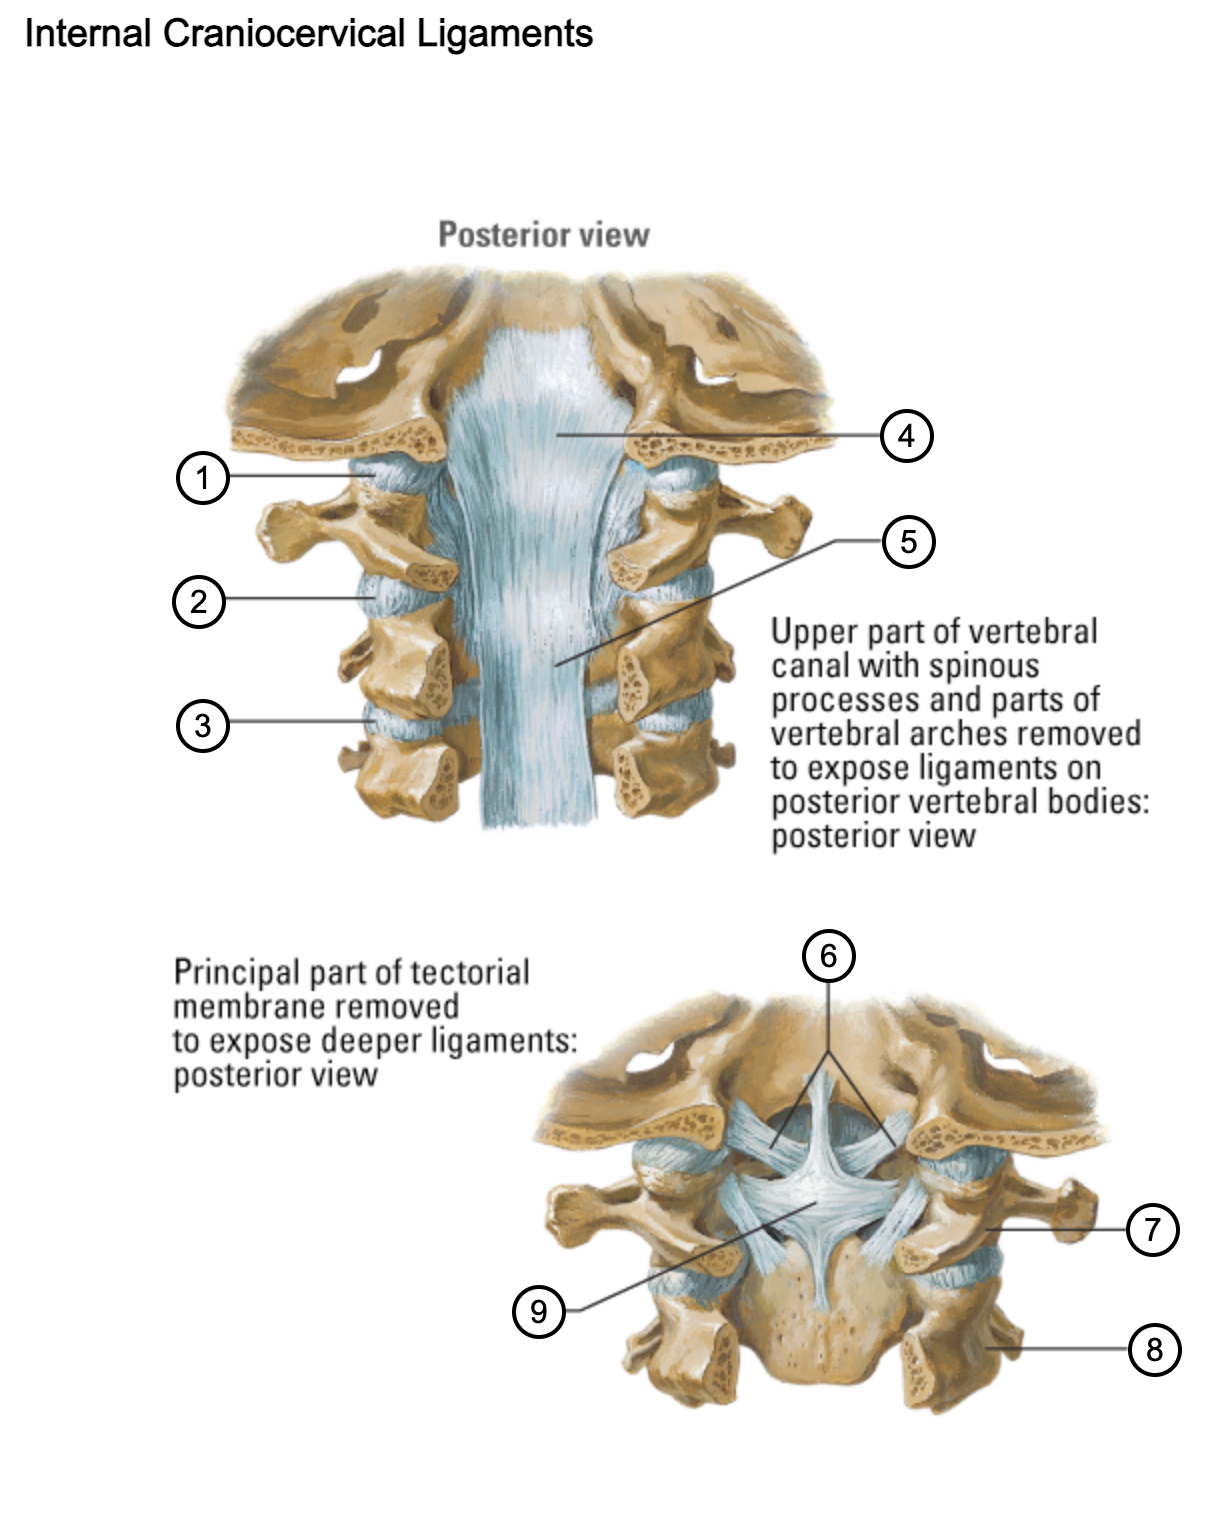

1

capsule of atlantooccipital joint

2

capsule of lateral atlantoaxial joint

3

capsule of zygapophysial joint (between axis and C3 vertebra)

4

tectorial membrane of cervical vertebral column

5

posterior longitudinal ligament

6

alar ligaments

7

atlas (C1)

8

axis (C2)

9

cruciform ligament (superior longitudinal band; transverse ligament of atlas; inferior longitudinal band)